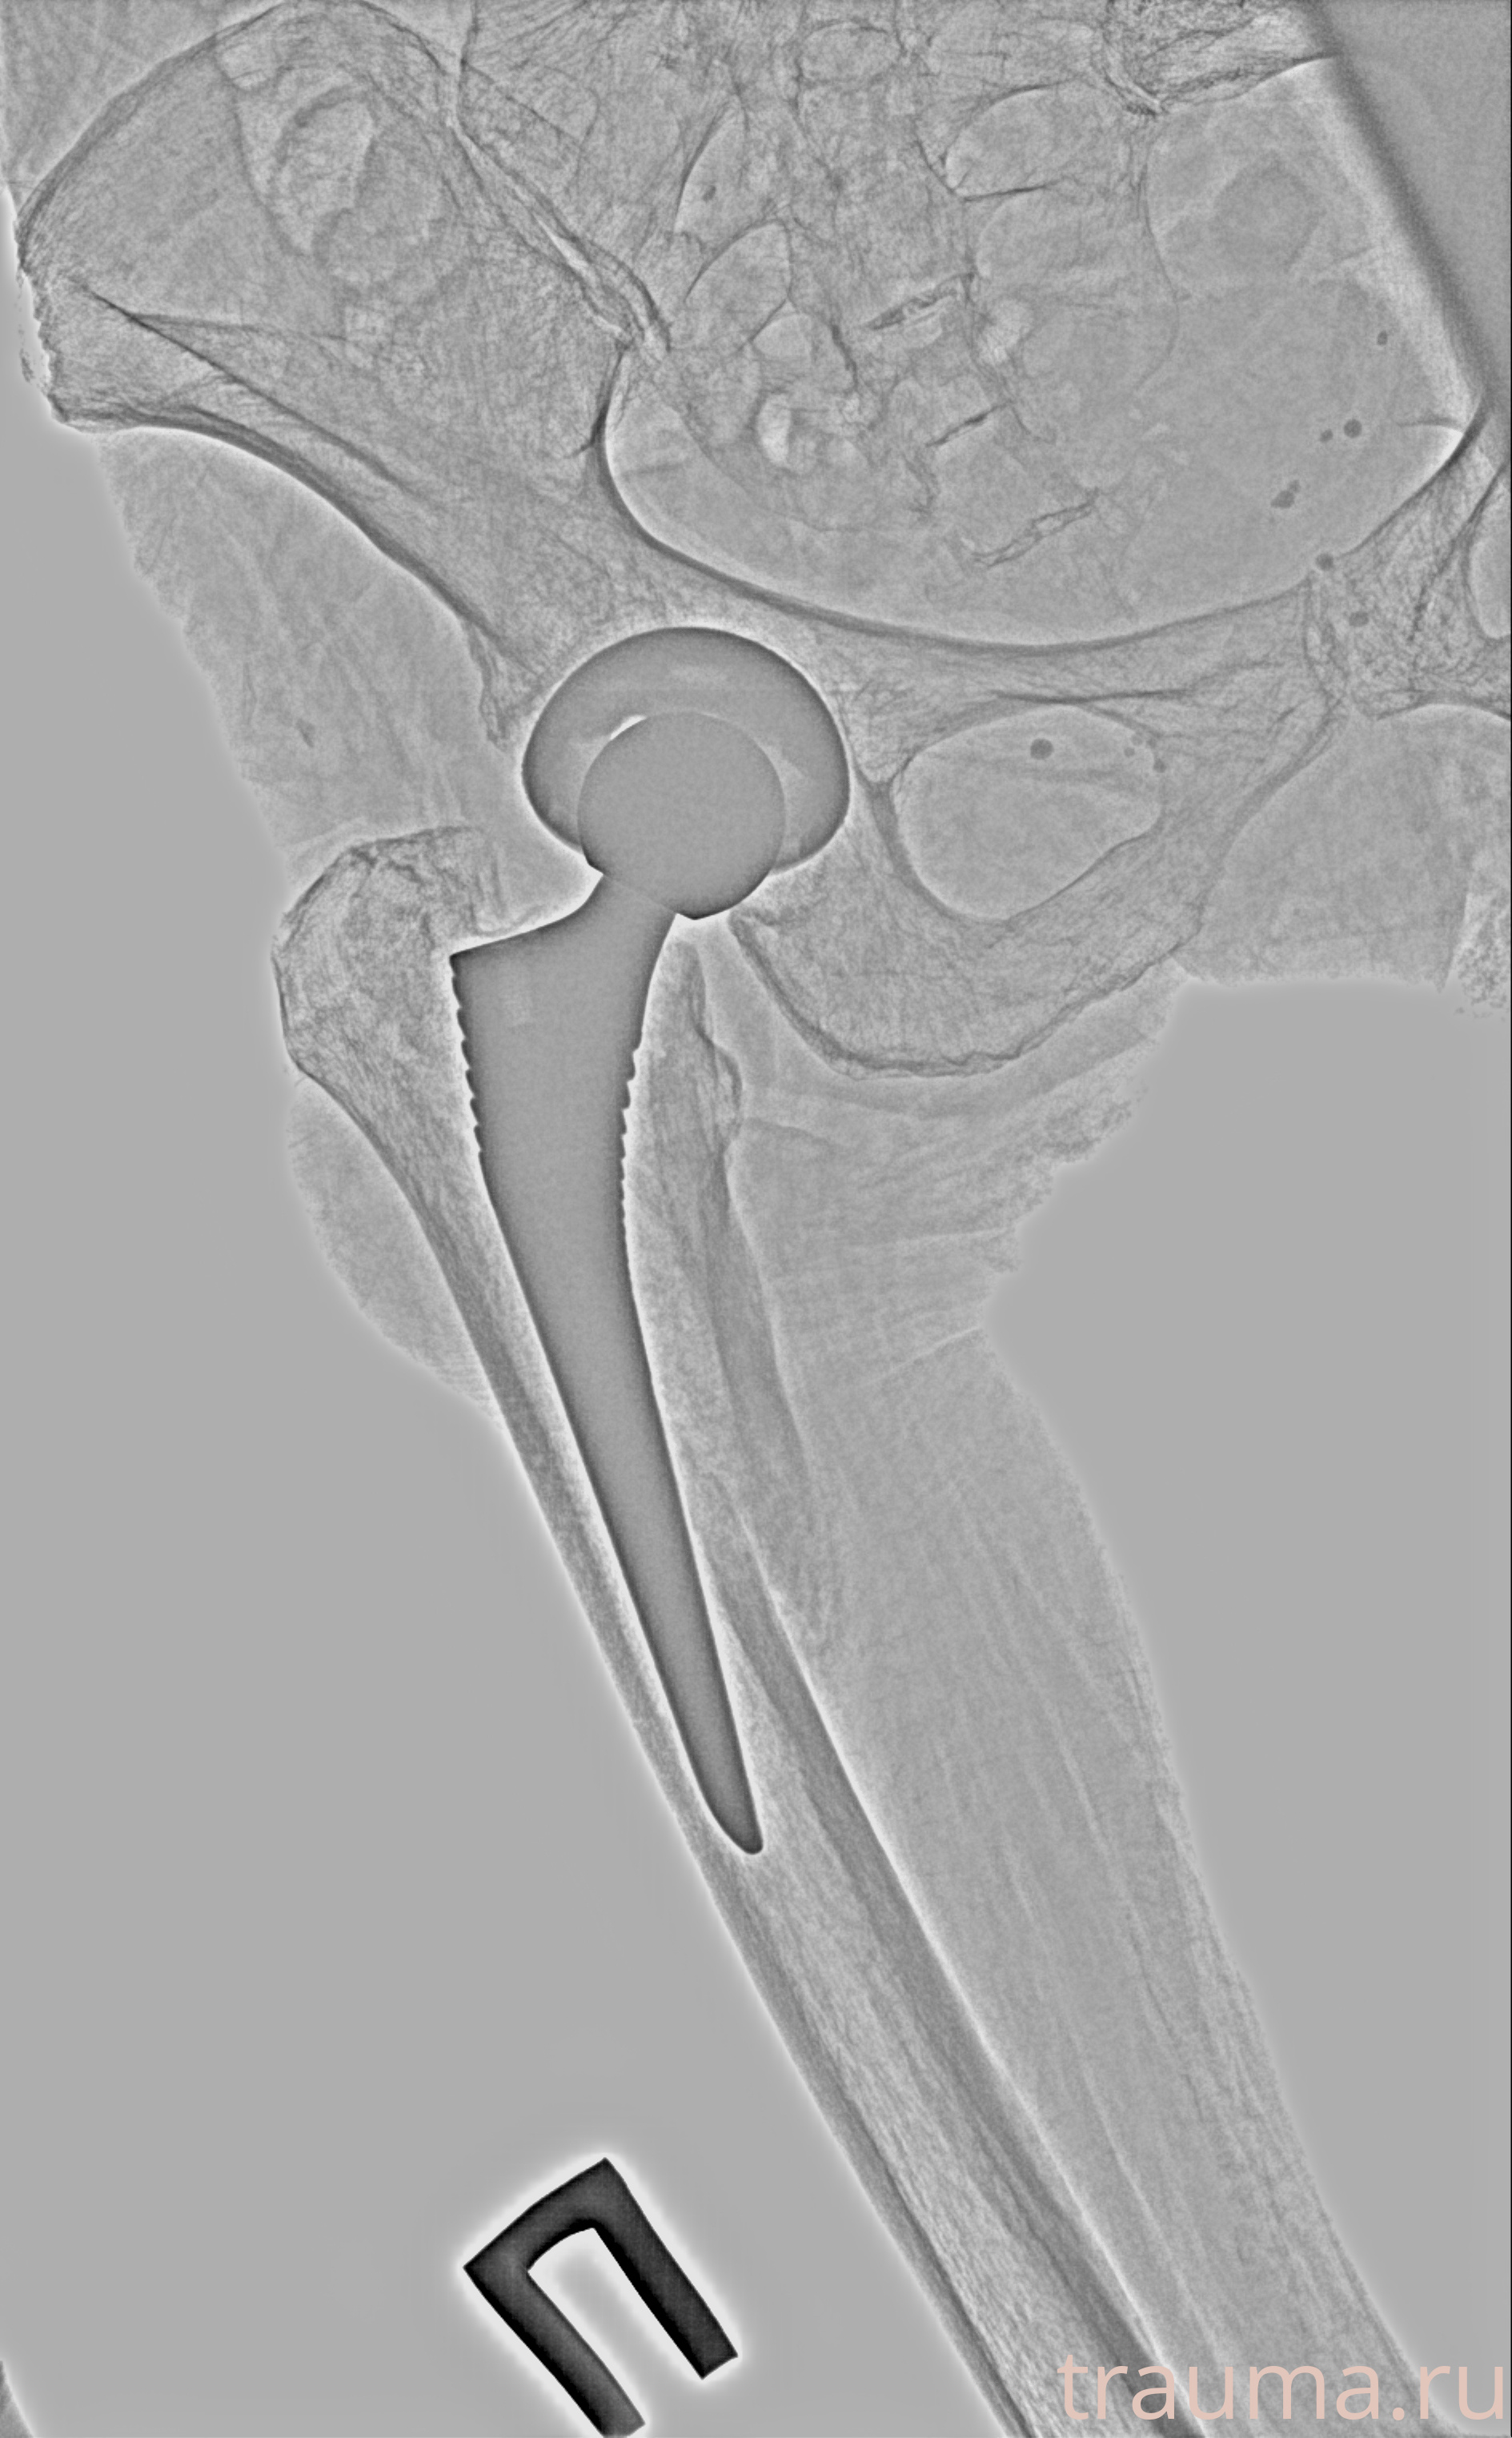

Рентгенограммы